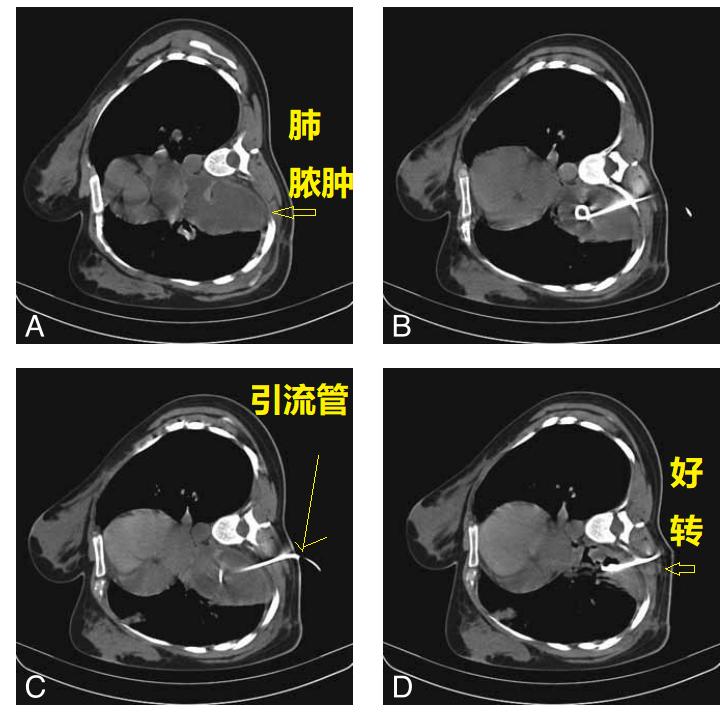

外院不知道为什么就考虑肺脓肿,还在“脓腔”里面放一大个引流管。这种骚操作,不容易见到。各位请看。

图02-05

首先,我们不得不承认,这个放引流管的水平,确实高!就像洲际导弹,准确的命中目标,引流管放在了空洞的正中央。

这个空洞,是个典型的肺鳞癌。根本就没有必要放个引流管。

首先,患者没有明显的感染症状!其次,这个空洞没有气液平,也不像肺脓肿。最后,这个空洞乱糟糟的,有些地方壁厚,有些地方壁薄,空洞里面凹凸不平,空洞周围边界清晰,没有炎症反应引起的模糊阴影。外加患者是中年人,基本上就是肺鳞癌。

这个引流管放进去,啥都没有引流出来,还导致了少量气胸。

图06

老年男性,抗生素治疗失败。CT示右下叶一大个脓腔。

图07

脓肿穿刺,放置引流管,3周后完全愈合。

图08

26岁女性,肺脓肿,抗生素治疗1周,仍然发热。

CT引导下,肺脓肿穿刺引流(下图B、C),术后随访,脓液完全引出(下图D)。

图09